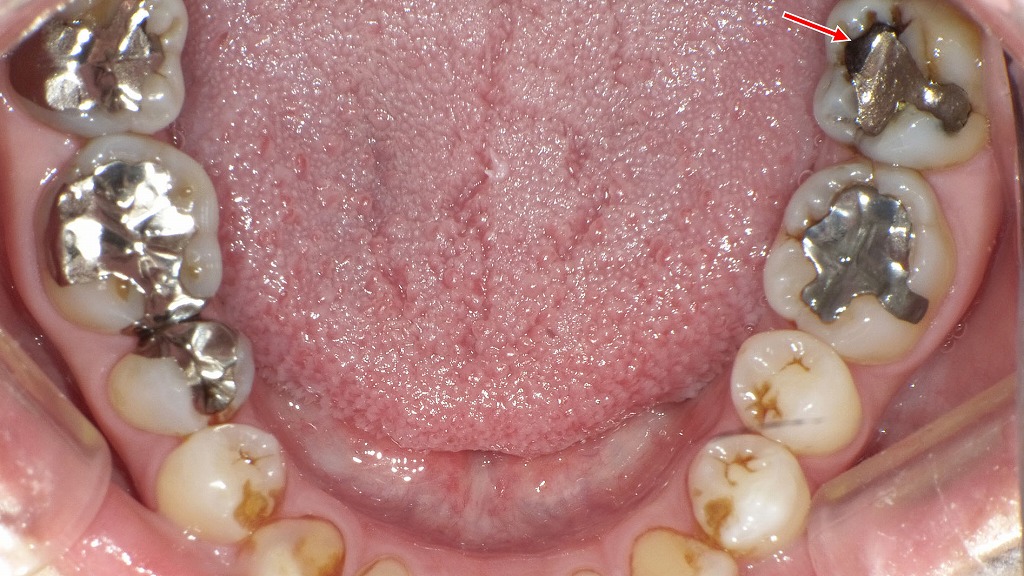

銀歯(メタルインレー)の隙間から細菌が侵入して二次カリエス(再発虫歯)が生じている状態です。金属修復物は長期使用により変形や破折が起こることがあり、見た目では分かりにくくても内部で虫歯が進行しているケースがあります。違和感や引っかかりを感じた場合は、早めのチェックが重要です。